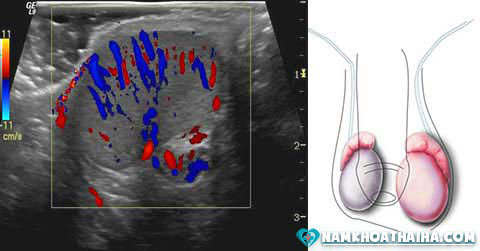

Siêu âm tinh hoàn